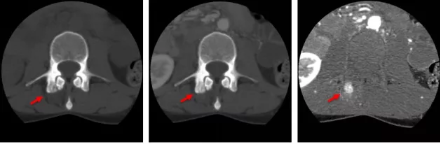

骨智能柔性減影成像功能發(fā)現(xiàn)隱匿骨占位病灶

相比傳統(tǒng)成像方式,肺部柔性減影技術通過人工智能,對平掃數(shù)據和CT肺動脈血管掃描數(shù)據進行智能比對,解碼并識別各個器官(肺、氣管、肺動脈、肺靜脈、主動脈等)的空間位置,并在三維空間中進行體素級的柔性配準,從而極大提升了不同序列數(shù)據的空間位置的一致性。通過肺部柔性減影技術可得到肺強化碘圖,可以顯示出傳統(tǒng)CTPA圖像看不到的小栓塞病變,提高了栓塞檢出率,其結果甚至可與SPECT吻合。